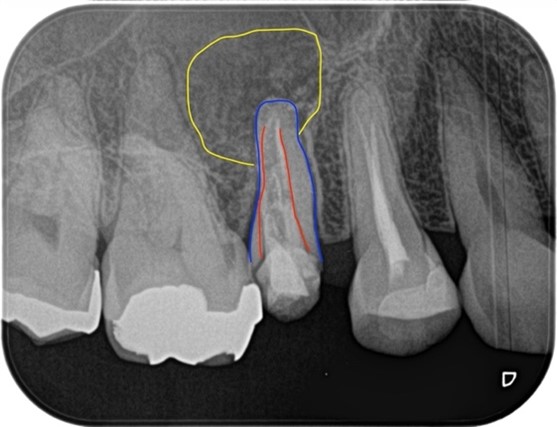

この患者様は、前医での根管治療がうまく行っていないことを主訴に当院の精密根管治療カウンセリングを受診されました。初診時の段階で歯肉の炎症が著しく、根尖部を指で押すと痛みを訴えておられました。診査したところ右上5番の根尖には黒い透過像(写真2黄色囲み線)が確認できるのと、歯質は大きく削られており(写真2赤線部)、残存する歯質は(写真2青線部)非常に薄くなっていることが確認できました。

初診の時点では破折等の所見は確認されなかったことら、治療は可能と判断しましたが、歯質が薄いことから将来的な費用対効果が低くなることも考えられました。